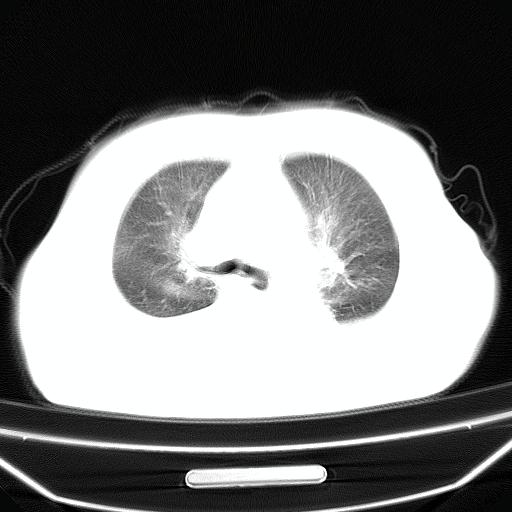

以下是引用liuyue在2008-4-19 22:25:00的发言:[br]先考虑:1.心衰伴肺水肿、双侧胸腔积液、叶间积液、双下肺不完全性肺不张; [br] 2.冠状动脉粥样硬化。

以下是引用jiangjing在2008-4-20 10:43:00的发言:[br]结合病史支持 冠心病[冠状动脉钙化],心功能不全,肺淤血、肺水肿,双侧胸腔与斜裂积液